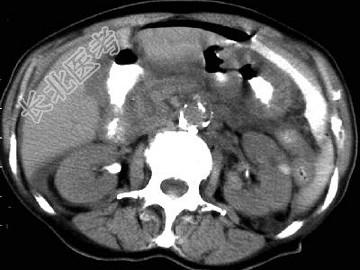

- 单项选择题男,44岁, 突然中上腹痛,压痛, 反跳痛,腹肌紧张, 发热,白细胞计数升高, CT检查如图,最可能的诊断是 ( )

A、急性胰腺炎

B、慢性胰腺炎

C、胃小弯溃疡穿孔

D、胰腺癌

E、胃癌